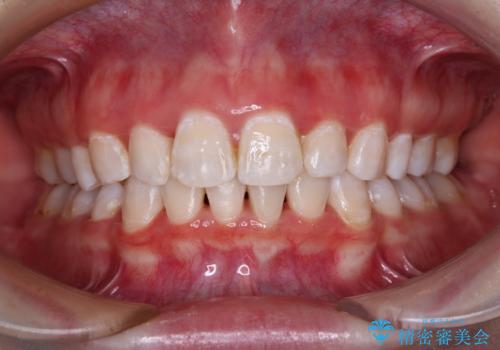

デコボコをワイヤー装置で改善 短期間で綺麗な仕上がりに

担当医 藤巻太一朗